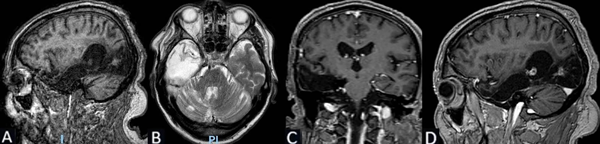

Se solicita RM de cerebro con contraste de cortes de 1 mm donde se objetiva lesión espontáneamente hipointensa en la secuencia T1 localizada en la región frontal derecha entre F1 y F2 de 3 x 2.25 x 2.84 cm. Hiperintensidad de la sustancia blanca subcortical en T2 de forma triangular con base hacia la corteza y vértice hacia la región ventricular (signo del transmanto), engrosamiento cortical focal, pobre delimitación entre la sustancia blanca y gris. Sin efecto de masa y escaso realce tras la administración del contraste (Figura 1).

Figura 1. Caso 1: RM de cerebro. A) Secuencia T1. Corte sagital. B) Secuencia T2. Corte axial. C) Secuencia T2. Corte coronal. D) Secuencia T1 con contraste. Corte axial.